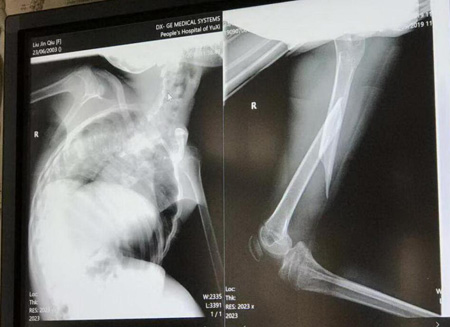

近日,一例16岁,体重仅有20公斤,胸廓脊柱四肢严重畸形,并极度营养不良的痉挛性脑瘫患者在玉溪市人民医院进行股骨干骨折的复位固定手术。

这位患者因股骨干骨折入院,痉挛性脑瘫16年,全身呈卷曲状态,体重仅有20kg,胸廓脊柱四肢严重畸形,因左侧股骨干骨折入院。